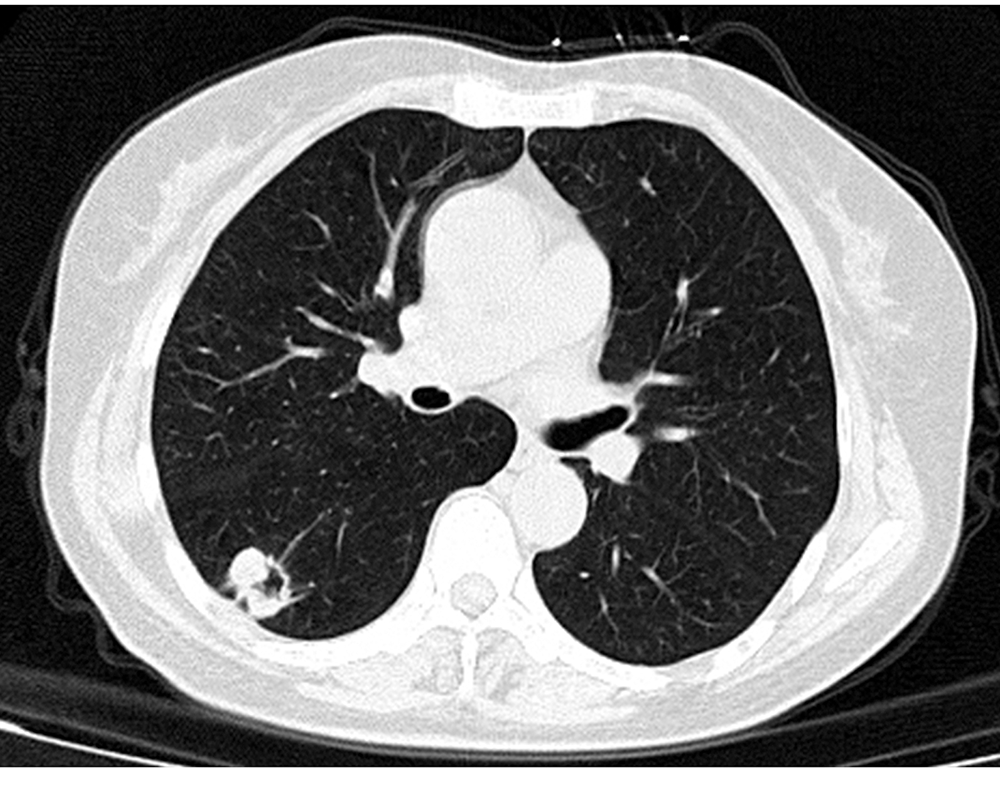

目的探讨肺部转移瘤非典型多层螺旋CT(MSCT)多形性表现与病理结果的相关性。方法收集2012年1月至2019年7月中国人民解放军中部战区总医院和陕西省肿瘤医院168枚肺部转移瘤的MSCT胸部影像学资料,根据病理类型分为转移性腺癌(88枚)及转移性鳞状细胞癌(80枚)。分别观察并记录两组肺部转移瘤非典型MSCT的影像学征象,逐一标记后归类,比较两组非典型MSCT影像特征间的差异,分析转移性腺癌及转移性鳞状细胞癌组内病灶大小与非典型MSCT影像特征的相关性。结果肺部转移性腺癌和转移性鳞状细胞癌毛刺征分别为61枚(69.32%)、28枚(35.00%),组间比较差异有统计学意义(χ2=19.811,P<0.001);胸膜凹陷征分别为48枚(54.55%)、16枚(20.00%),组间比较差异有统计学意义(χ2=21.206,P<0.001);空泡/空洞征分别为10枚(11.36%)、61枚(76.25%),组间比较差异有统计学意义(χ2=72.303,P<0.001);含气支气管征分别为43枚(48.86%)、13枚(16.25%),组间比较差异有统计学意义(χ2=20.057,P<0.001);晕征/磨玻璃影分别为58枚(65.91%)、37枚(46.25%),组间比较差异有统计学意义(χ2=6.591,P=0.010)。Spearman秩相关分析显示,转移性腺癌结节大小与毛刺征、胸膜凹陷征呈正相关(r=0.270,P=0.011;r=0.226,P=0.035);转移性鳞状细胞癌结节大小与非典型MSCT影像特征均无关(均P>0.05)。结论肺部转移性腺癌非典型MSCT多表现为毛刺征、胸膜凹陷征、含气支气管征及晕征/磨玻璃影,转移性鳞状细胞癌多表现为空泡/空洞征。毛刺征、胸膜凹陷征与肺部转移性腺癌结节大小有相关性。

ObjectiveTo investigate the correlations between multi-slice spiral CT (MSCT) atypical pleomorphic signs and pathological findings of lung metastases.MethodsFrom January 2012 to July 2019, the MSCT chest imaging data of 168 metastatic tumor of lung from the General Hospital of Central Theater Command of the Chinese People's Liberation Army and Shaanxi Provincial Tumor Hospital were collected. According to the pathological type, they were divided into metastatic adenocarcinoma group (n=88) and metastatic squamous cell carcinoma group (n=80). The atypical imaging signs of MSCT of the two groups were observed and recorded, and classified after labeling one by one. The difference of atypical MSCT imaging features between the two groups was compared, and the correlations between lesion size and atypical imaging features of MSCT in the metastatic adenocarcinoma group and metastatic squamous cell carcinoma group were analyzed.ResultsThe spicule sign in metastatic adenocarcinoma and metastatic squamous cell carcinoma were 61 (69.32%) and 28 (35.00%), with a statistically significant difference (χ2=19.811,P<0.001). The pleural depression sign in the two groups were 48 (54.55%) and 16 (20.00%), and there was a statistically significant difference (χ2=21.206,P<0.001). The vacuole/cavity sign in the two groups were 10 (11.36%) and 61 (76.25%), and there was a statistically significant difference (χ2=72.303,P<0.001). The air bronchial sign in the two groups were 43 (48.86%) and 13 (16.25%), with a statistically significant difference (χ2=20.057, P<0.001). The halo sign/ground glass shadow in the two groups were 58 (65.91%) and 37 (46.25%), with a statistically significant difference (χ2=6.591,P=0.010). The results of the Spearman rank correlation analysis indicated a positive correlation between the size of metastatic adenocarcinoma and spicule sign, pleural depression sign (r=0.270,P=0.011;r=0.226,P=0.035). There was no correlation between the nodule size and atypical MSCT imaging features in metastatic squamous cell carcinoma (allP>0.05).ConclusionThe atypical MSCT of metastatic lung adenocarcinoma are mostly spicule sign, pleural depression sign, air bronchial sign and halo sign/ground glass shadow. The characteristic atypical imaging of metastatic squamous cell carcinoma is vacuole/cavity sign. The spicule sign and pleural depression sign are related to the size of metastatic lung adenocarcinoma nodules.